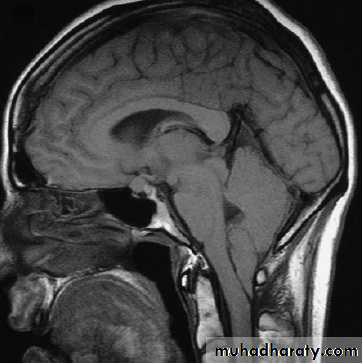

NEUROIMAGINGX-rays (plain X-rays, computed tomography (CT), myelography and angiography), magnetic resonance (MR imaging-MRI, or MR angiography-MRA), ultrasound (Doppler imaging of blood vessels), and radioisotopes (single photon emission computed tomography-SPECT, and positron emission tomography-PET).